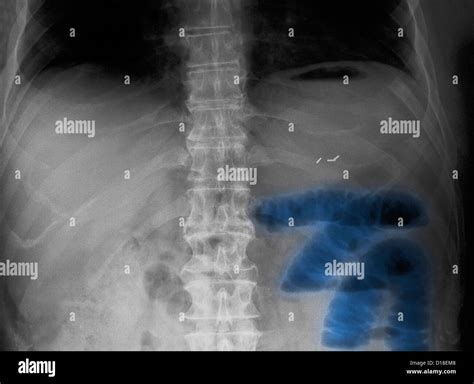

Doctors typically use a combination of physical exams and imaging technology to confirm an obstruction. A physical examination focuses on listening for high-pitched bowel sounds or silence, which helps differentiate between mechanical and functional issues. The following table summarizes the diagnostic methods used to evaluate intestinal distress:

Abdominal X-ray Detects trapped gas and dilated bowel loops.